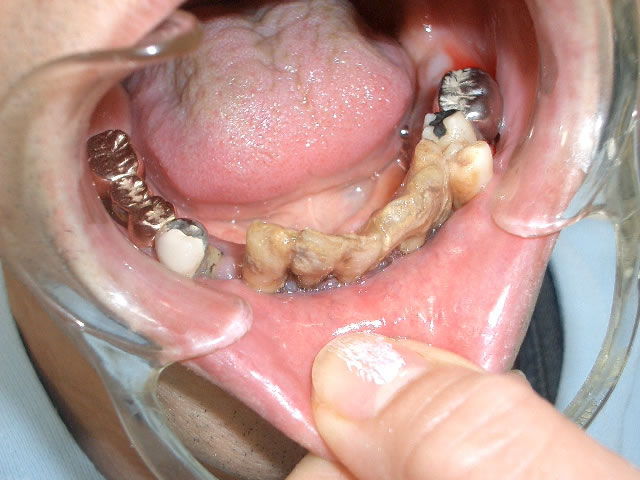

- 口の中の状態

- 口の中をのぞいてみたら、歯がまだ十分残っているようですが・・・